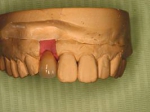

義歯の内面(内側に赤いプラスチックが見えますがこれが消耗品で半年に一度くらい交換すれば元の維持が復活します。)